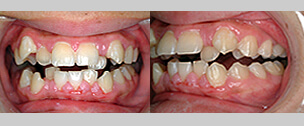

悪い歯並びや噛み合わせを、きちんと噛み合うようにして、きれいな歯ならびにする歯科治療です。悪い歯並びや噛み合わせをそのままにしておくと、食べ物がよく噛めない、発音が不明瞭である、むし歯や歯周病になりやすい、口臭の原因になる、アゴの関節に負担をかける、歯を折りやすいなどさまざまな問題が生じるとされております。矯正治療を行うことで、これらの問題を解決し、美しい笑顔と健やかな口腔環境をつくることができます。

顎への負担を軽減し、噛めるということ

本来すべての歯で均等に噛むことが理想ですが、全体に噛むのではなく、まず不正な位置にある歯があたってしまうことがあります。このままにしておくと、強くあたる歯が欠ける、削れる、アゴが痛くなるなどの症状が現れてしまいます。

矯正治療では、「よく噛める」ように機能回復をはかることも目標のひとつです。